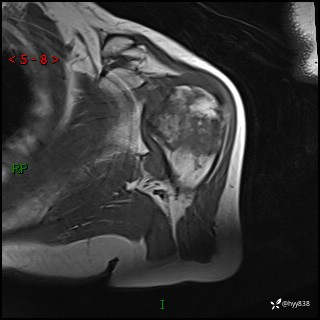

肱骨MRI平扫(axi T1WI+cor T2WI-fs)+CE-fs(COR+SAG)

现病史:患者1月前无明显诱因出现左肩关节疼痛,于2024.07.31就诊于我院骨科门诊完善左肩关节MR:左肱骨头信号异常,肿瘤?建议进一步检查。左肩关节积液。左腋窝淋巴结增大。今为求明确诊断就诊我科,门诊以“骨质破坏”收入我科。 起病以来,精神食欲睡眠尚可,大小便正常,体力体重无明显变化。